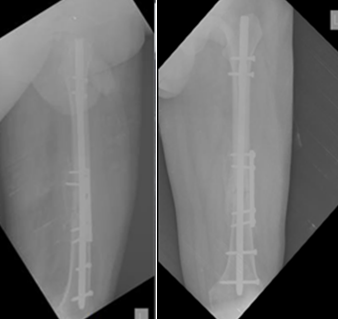

None of the patients experienced post-operative knee or hip stiffness after undergoing combination fixation with an intramedullary nail and derotation plate. X-rays of the patient with follow-ups at 3 months and 6 months(Fig. 1, 2, 3, 4).

Figure 2: Showing immediate post-operative X-rays.